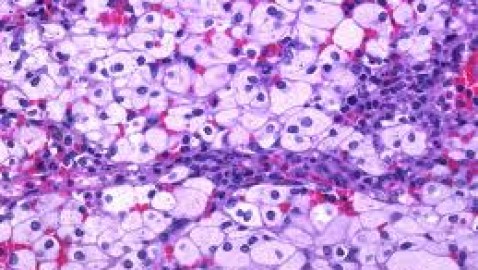

Enfermedad de Niemann-Pick. Los pacientes presentan notable aumento del tamaño del hígado y bazo. Las células del hígado y bazo tienen aspecto moteado, y se acumula gran cantidad de esfingomielina en los tejidos. El defecto primario es la falta de esfingomielinasa, enzima que cataliza el primer paso catabólico de la esfingomielina.

Enfermedad de Gaucher. Los individuos afectados presentan hepatoesplenomegalia y células características, cargadas de lípidos, en distintos tejidos y en la médula ósea. En el tipo más frecuente de esta enfermedad no hay compromiso de sistema nervioso. Se acumulan en las células glucocerebrósidos, no degradados por la falta de glucocerebrosidasa.